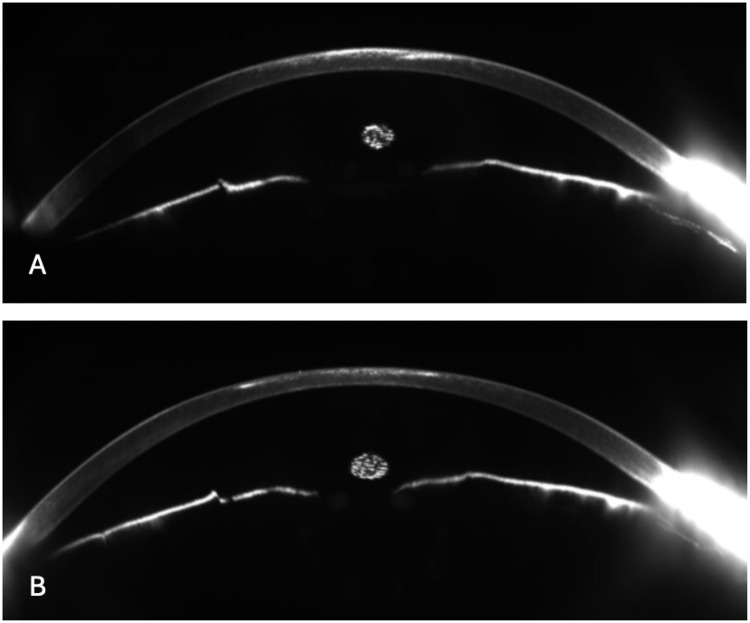

Results: A 27-year-old woman was referred to our clinic for Acanthamoeba keratitis in her left eye. After 1 year from the infection, the patient returned to our attention for developing a central corneal scar and decreased corrected distance visual acuity (CDVA) in the left eye. The slit-lamp examination showed a central corneal opacity involving anterior stroma. A single-step topography-guided trans-epithelial PRK combined with PTK (CIPTA®2 software, iVis Technologies) was performed in the left eye. After surface ablation using PRK, PTK was performed using masking agents (1% hydroxymethylcellulose) to smooth the ablated surface. Subsequently, 0.02% Mitomycin C was applied over the ablated surface. At the 1-month follow-up, a resolution of the corneal opacities was observed, with a visual improvement to 20/20, which was maintained at the 3-, 6-, and 12-months follow-up. Furthermore, there was an improvement in spherical equivalent and corneal morphological irregularity index.

Conclusion: Corneal opacity following AK may be successfully treated using a combined topography-guided trans-epithelial PRK and PTK in selected patients.